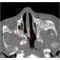

When deciding on the technique of the surgery, the location of the hole on the membrane, the width of the ear canal, whether there is disease in the ear bone, the presence of cholesteatoma, and the surgeon’s preferences are taken into consideration. Under these conditions, with an 3-4 centimeters incision made behind the auricle or with a smaller incision in front of the ear, or by working only inside the ear in cases of very simple perforation, this eardrum surgeries can be performed. The most frequently used tissues in repairing the eardrum are the sheath of the temporal muscle or the cartilage tissue taken from the structure called tragus in the ear entrance. Since these tissues are very close to the surgical field, they can be easily obtained during surgery.